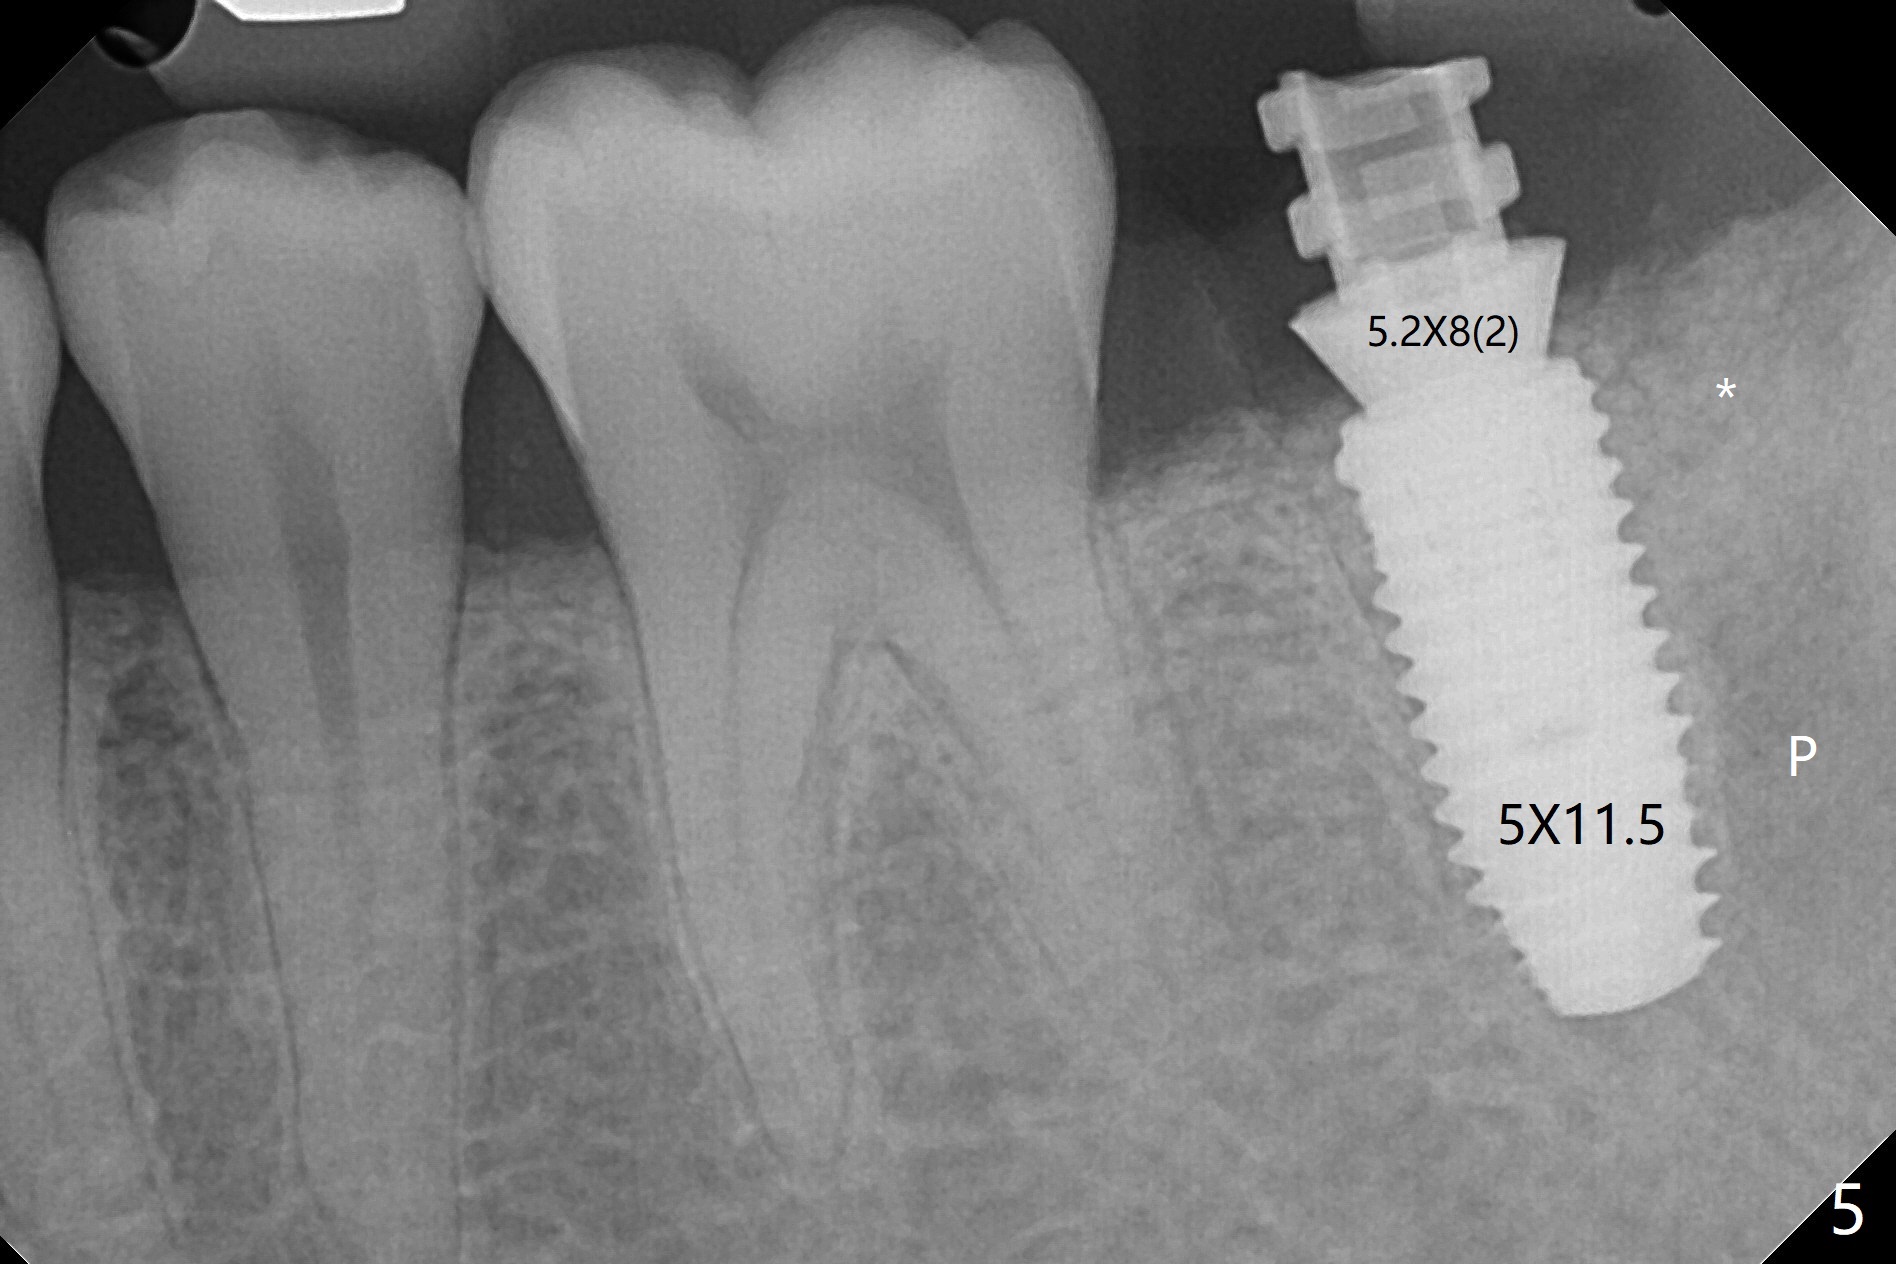

即刻种植即刻修复偶尔出现骨粉丧失,今天我们尝试临时基台,它可以制作像螺丝固位牙冠,可能会减少骨粉流失。左下7颊侧肿胀(图一:*),为了让植体(图二:绿色)植入中隔正中,钻洞时保留近中(M),远中(D)牙根。但是意想不到的是在导板指引下,钻头还是偏移近中(图三),而且颊侧(图四:圆圈),不过颊侧骨板没有缺损。由于牙根存在(硬),钻洞吃力,之后拔除,完成最后一个钻头,放置植体(图五),方位仿佛不错,临时基台(5.2x8(2)毫米)也完全就位,树脂围绕基台制作临时牙冠(图六),最后使用螺丝固位(*),颊侧肿胀牙龈必须用缝线固定(<),减少骨粉损失。由于牙冠与基台连接不好,病人汇报有些骨粉丢失。术后一个月检查尚可愈合正常,病人满意,已经做好思想准备做右下第二磨牙种植。临时牙冠进行修整。术后即刻近中牙槽窝间隙由粘性骨粉充填(图五),四个月后间隙消失(硬骨板也消失,图七),5.2x5(3)毫米粘固基台似乎没有完全就位,可能因为远中牙槽嵴阻挡(图七:*)。小一号基台仿佛完全就位(图八(咬翼片);图七(根尖片,可能失真)),但是临床上没有听到清脆声音(可能软硬组织阻挡)。随着时间推移,远中牙槽嵴吸收,当松动基台螺丝再次拧紧,可能会真正完全就位,必须拍摄完美咬翼片证实。这种植体芯(body, not threads)特别厚内部结构看不清楚。两周后粘固牙冠,然后取出牙冠和基台,清除残余粘固剂,然后复位,拧紧30Ncm。